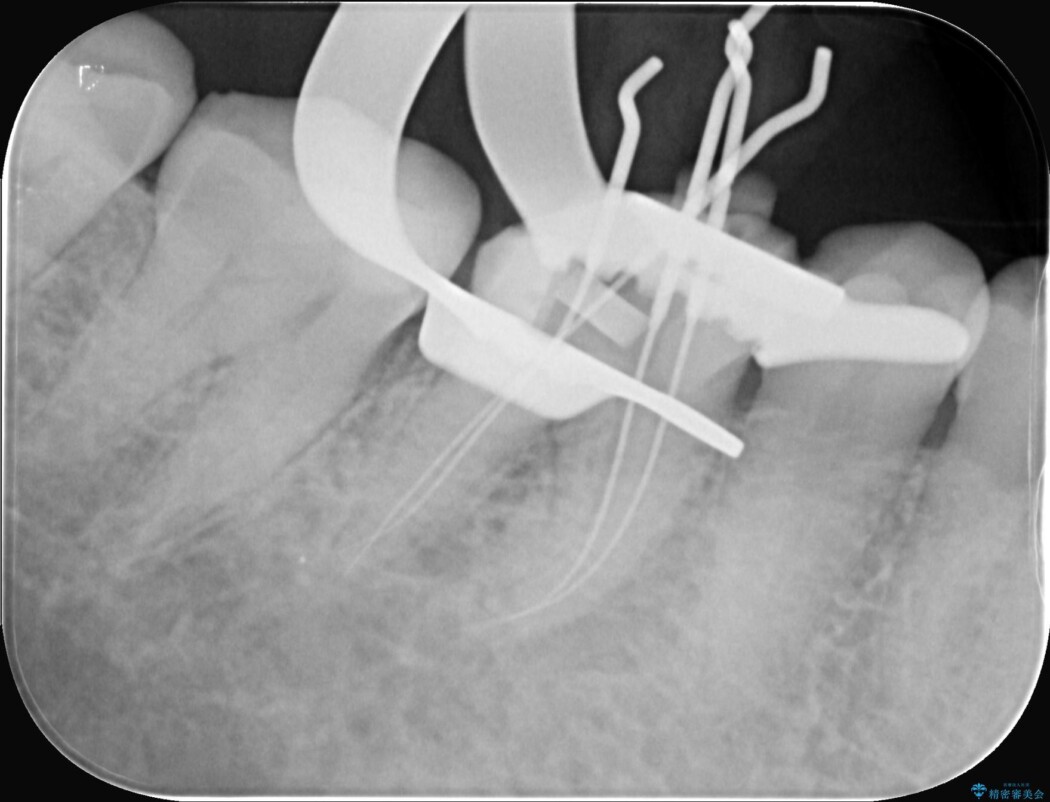

治療では、マイクロスコープで根の中を大きく拡大し、非常に細くなっていた神経の通り道を慎重に見つけ出しました。

次に、根のカーブに沿ってしなやかに曲がるニッケルチタンファイルを使い、根の先まで徹底的に洗浄・殺菌を行いました。汚れを完全に取り除いた後、隙間なくお薬を詰めて密閉しています。